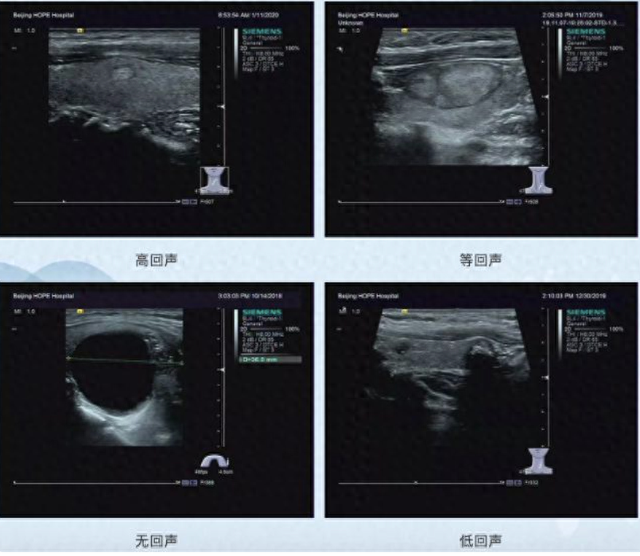

二、听回声:结节内部的 “健康密码”

高回声常见于良性胶质囊肿,可通过化痰祛湿调理;

低回声与痰瘀阻滞有关,恶性倾向大;

极低回声提示内部复杂,发现后立即就医。